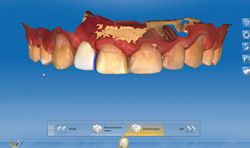

Fig 2, 2a (below) A virtual tooth (digital wax-up) was designed for the patient using the CEREC 4.4 software.